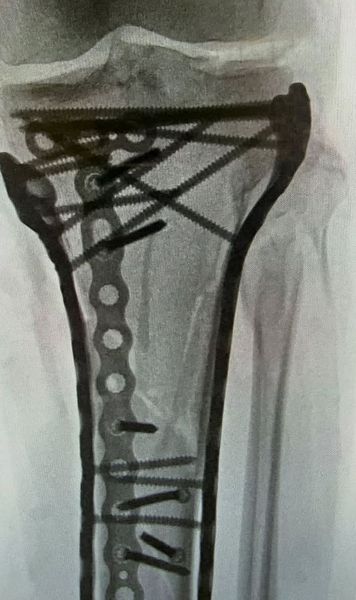

Radiografia lui Lindsey Vonn!    FOTO.  Schioarea americană, operată a 5-a oară:   „Sunt bionică acum”